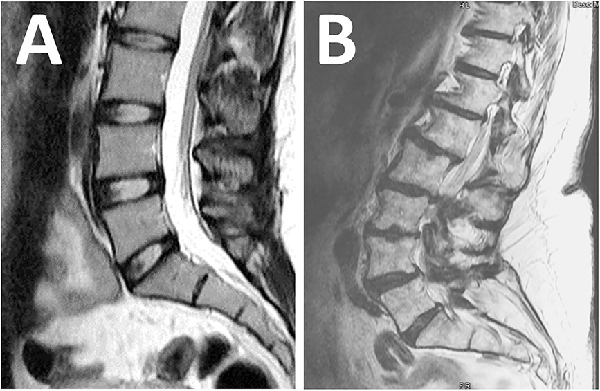

Figure 3

Magnetic resonance imaging: (A) normal findings with no pathology; (B) abnormal findings with multiple abnormalities not suitable for surgery.